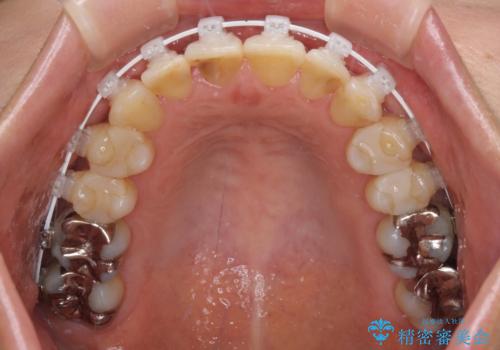

- 矯正装置

- 審美装置

- 治療期間

- 1年10ヶ月

舌突出癖により、上下前歯がなかなか接触せずに治療期間を要しましたが、舌のトレーニングにより無事に治療を終えることができました。